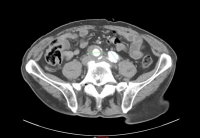

Filmbeispiel:

- infrarenales AAA, Durchmesser 54,2 mm

- Aneurysma der A. iliaca communis rechts, Durchmesser 41,1 mm